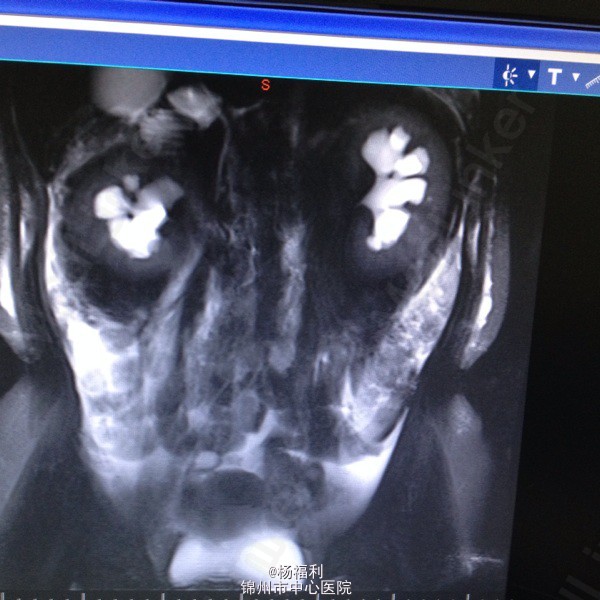

44岁女患。为消化科我会诊患者。 现病史:以上腹痛9小时为主诉入院。无发热及寒战、噁心未呕吐,无腹泻及黑便。 既往史:双眶炎性假瘤2年,口服激素治疗,并补钾。

查体:上腹部压痛,无反跳痛、右侧压痛明显,右肾区叩击痛,左肾区轻叩击痛,双输尿管走形区无压痛。 辅助检查;泌尿系彩超:双肾积水。 血白细胞:9.99*10^9。 肾功能正常。 全腹部ct及MRU检查:见图片。

诊断;真的不知道是啥病。 处理:暂时止痛处理。双肾病变。不知从哪里下手。